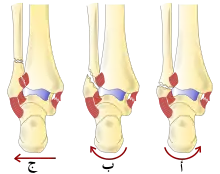

هناك العديد من التصنيفات لكسور الكاحل:

- تصنيف لوج هانسن، وهو يصنف كسور على أساس آلية الإصابة من حيث صلتها بموقف القدم والقوة المشوّهة.